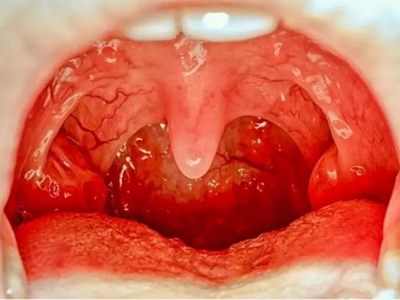

急性咽炎是咽黏膜、黏膜下组织的急性炎症,多累及咽部淋巴组织。此病可单独发生,亦常继发于急性鼻炎或急性扁桃体炎,常见于秋冬季及冬春季之交。患者主要症状为咽痛,检查可见咽部黏膜充血、水肿,需要多饮水,配合抗菌或抗病毒治疗。

急性咽炎起病较急,先有咽部干燥、灼热,继有明显咽痛,吞咽时尤重,有时可伴有发热、头痛、食欲减退和四肢酸痛等。检查可见口咽部黏膜呈急性弥漫性充血、肿胀,咽后壁淋巴滤泡隆起,表面可见黄白色点状渗出物。

可伴随悬雍垂及软腭水肿,下颌下淋巴结肿大、压痛。鼻咽及喉咽部亦可呈急性充血,严重者可见会厌水肿。